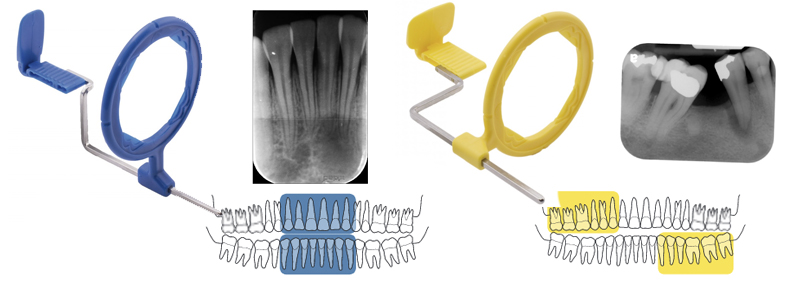

Le système XCP est classé par couleurs en fonction de l’emplacement et du traitement à effectuer :

- Le XCP Rouge est conçu pour la prise de radiographie bite-wing ou rétro-alvéolaire, un type spécial de radiographies du secteur postérieur où les deux arcs sont photographiés en occlusion. C’est aussi l’un des meilleurs outils pour le diagnostic des caries interproximales

- Le XCP Vert est conçu pour la prise de radiographies endodontiques où une disposition spéciale est nécessaire pour que l’image montre la dent avec la racine et l’apex dans sa totalité, et pour pouvoir diagnostiquer les maladies et visualiser les limes à l’intérieur du canal radiculaire.